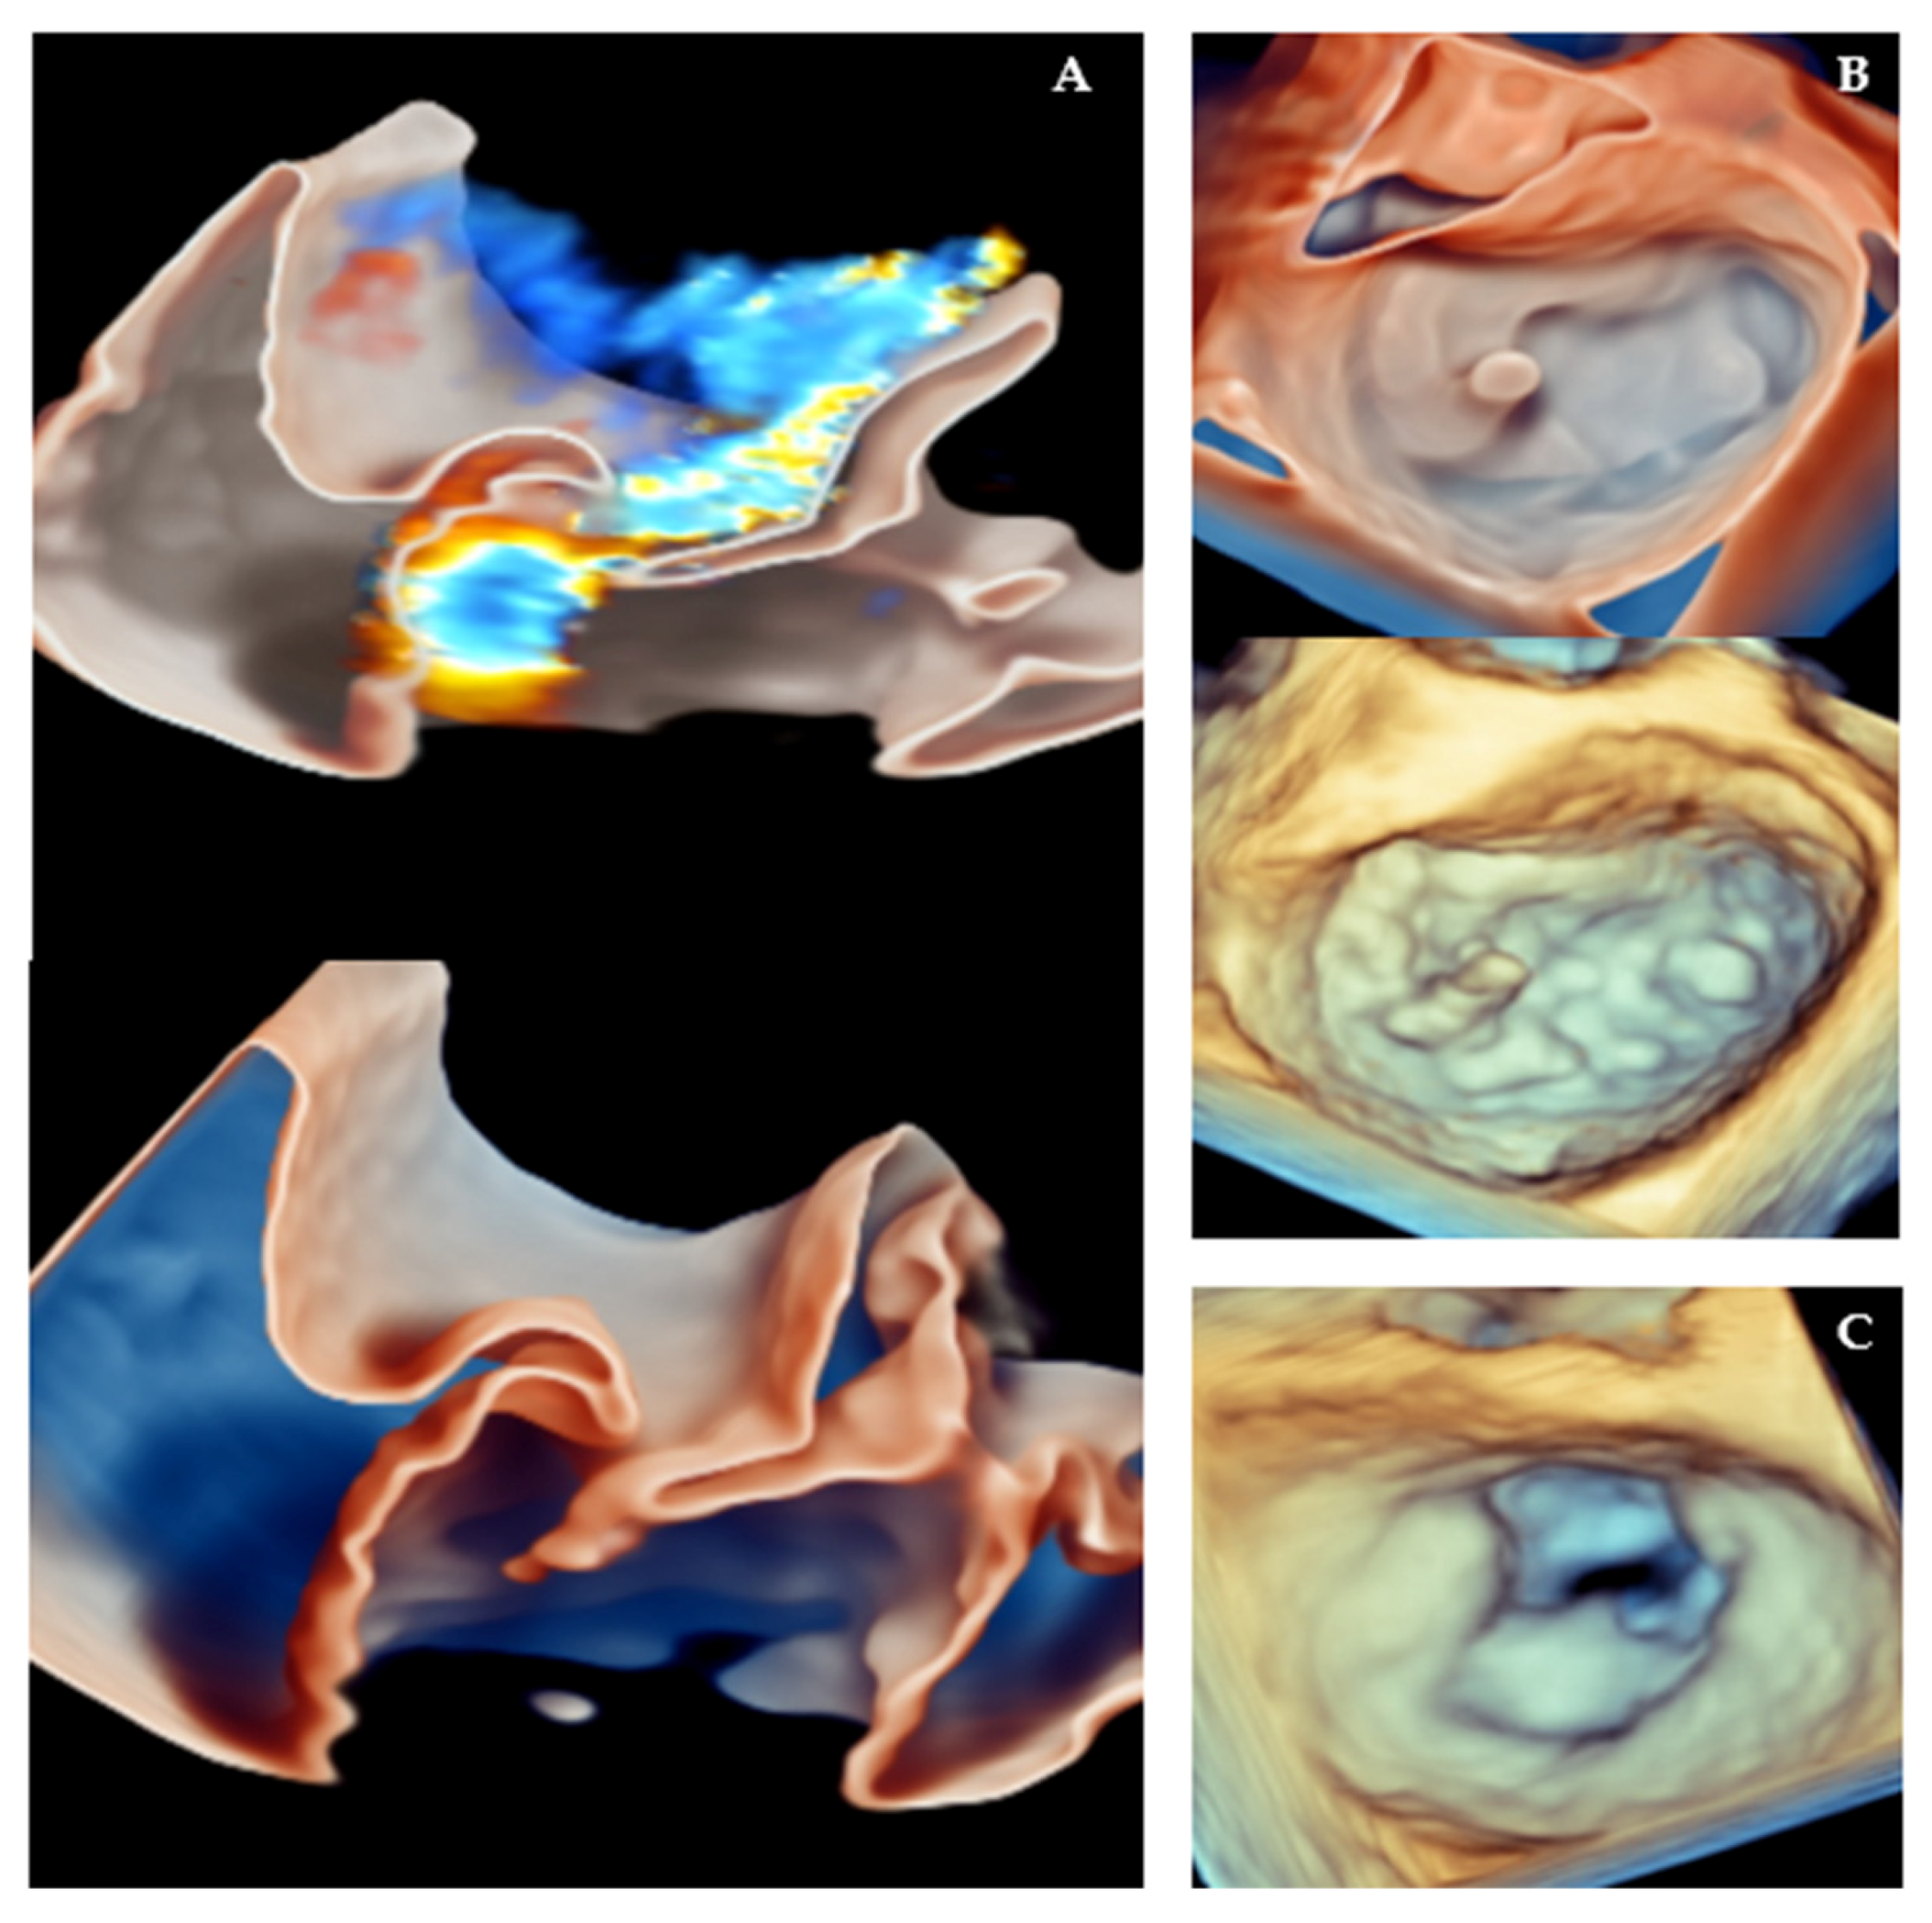

- Faletra, F.F.; La Franca, E.; Leo, L.A.; Sade, L.E.; Katz, W.; Musumeci, F.; Gandolfo, C.; Pilato, M.; Cipriani, M. The Key Role of 3D TEE in Assessing the Morphology of Degenerative Mitral Valve Regurgitation. J. Cardiovasc. Dev. Dis. 2024, 11, 342. [Google Scholar] [CrossRef]